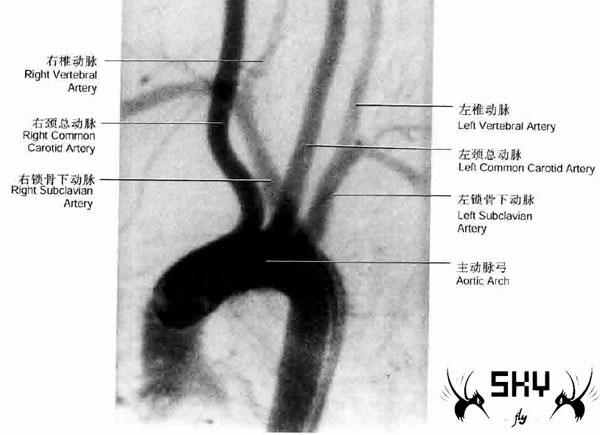

头颈部动脉血管形成于主动脉弓的三个主要动脉。2/3的人群中,头臂干是起自主动脉弓的第一条血管,左颈总动脉为第二条,左锁骨下动脉为第三条。右颈总动脉起自头臂干分叉处,右椎动脉起自头臂干的另一分支–右锁骨下动脉。左颈总动脉由主动脉弓直接向上发出,左侧椎动脉起自左锁骨下动脉。如下图:

CA